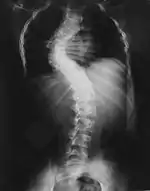

Проявления нейрофиброматоза I типа часто начинаются со сколиоза (искривления позвоночника), затем возникают трудности в обучении, проблемы со зрением и эпилепсия.

Костные изменения

Для выраженного нейрофиброматоза характерна деформация позвоночника в виде сколиоза, возможны краевые дефекты тел позвонков, их суставных и поперечных отростков, расширение межпозвоночных отверстий и эрозии их краёв, узуры нижних краёв задних отделов рёбер, вызванные давлением нейрофиброматозных узлов[36].